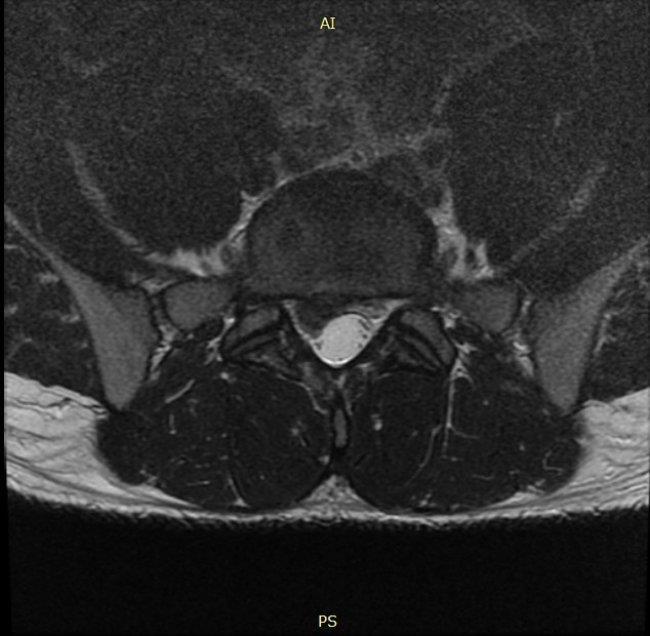

U chorego, który zgłosił się do lekarza specjalisty rehabilitacji medycznej z objawami bólu krzyża promieniującego do prawej kończyny dolnej i osłabioną siłą stopy prawej od kilku dni, a w badaniu stwierdzono siłą mięśniową zginaczy podeszwowych 3 wg Lovetta, brak odruchu ze ścięgna Achillesa i następujący obraz badania NMR wykonanego w drugim dniu po pierwszych objawach choroby, należy zlecić:

Pytanie 69